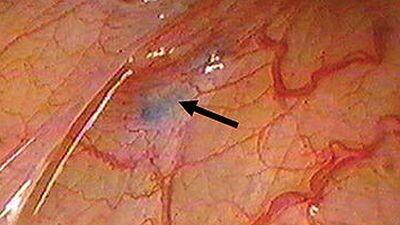

Sageli räägitakse endometrioosist kui ainult emaka haigusest. Minu kogemuse põhjal on pilt, aga laiem. Endometrioosi juured võivad olla seotud maksaga, mis on ülekoormatud. Kuna emakas puhastab naise keha igakuiselt ja väljutab verd, jääb organism siiski koormuse alla – maks ja põrn ei suuda piisavalt uut verd toota ega ka puhastada, kui vana veri ringleb endiselt kehas. See omakorda tekitab palju pahandus kehas.

Meie organid on tihedalt seotud hormoonidega ning hormonaalne süsteem juhib paljusid keha funktsioone. Keha toimib tervikuna – kui liikumismehhanismis tekib häire, ei piirdu see ainult ühe organi või piirkonnaga. Tasakaalu puudumine organite ja süsteemide vahel viib korrapärase funktsioneerimise häirumiseni. See tähendab, et endometrioosi või muude terviseprobleemide puhul ei saa vaadata ainult ühte organit, vaid tuleb arvestada kogu organismi tasakaalu ja toimimist.

Endometrioos ja paljud teised terviseprobleemid ei ole ainult ühe organi mure, vaid seotud kogu keha tasakaalu ja hormonaalse süsteemi toimimisega. Keha on tervik, kus iga häire mõjutab mitut süsteemi korraga. Seetõttu ei pruugi lahendus olla organi eemaldamine, vaid hoopis tasakaalu taastamine ja keha terviklik toetamine.